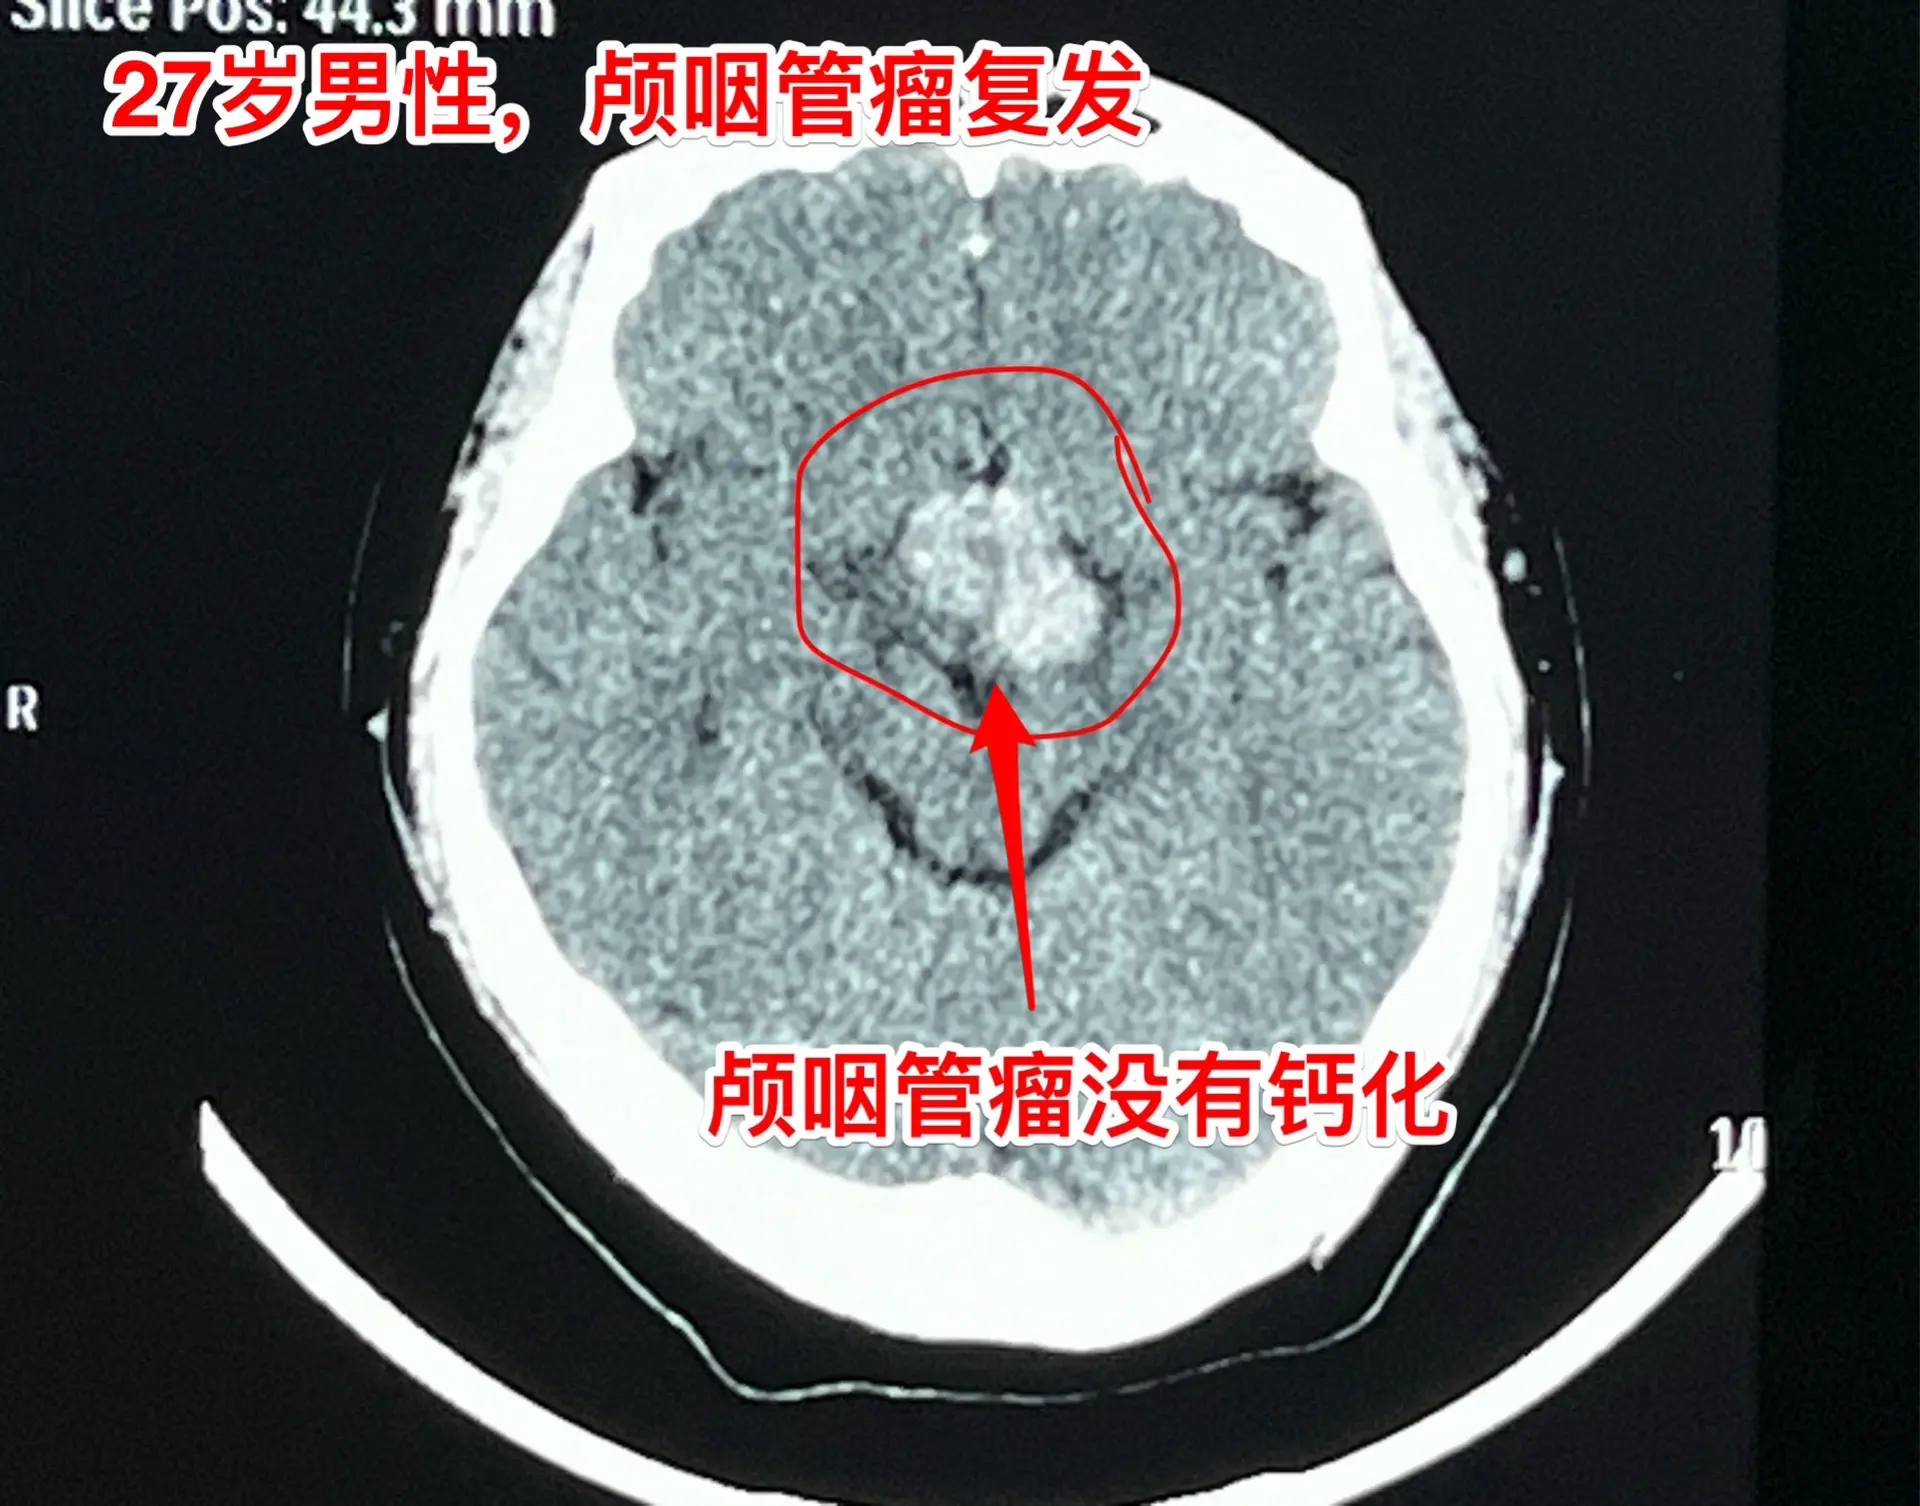

头CT显示肿瘤密度稍高,没有钙化,见图5。患者视力很差,根本看不见视力表的第一行。看手机时手机几乎是贴着眼睛才能看见。